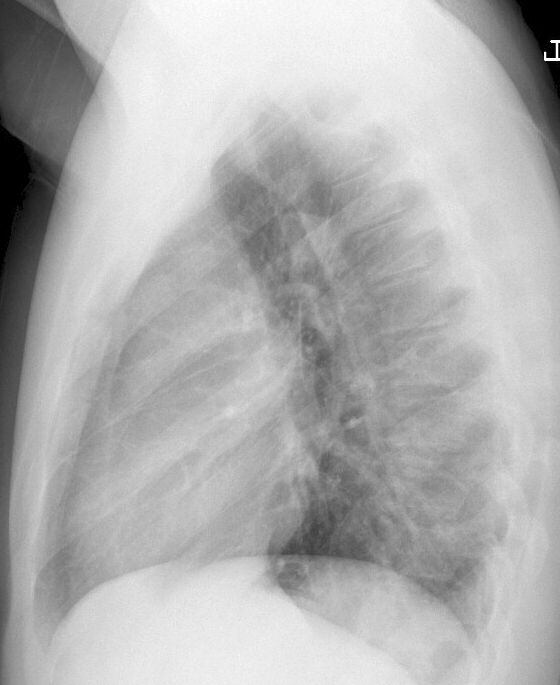

Thymoma